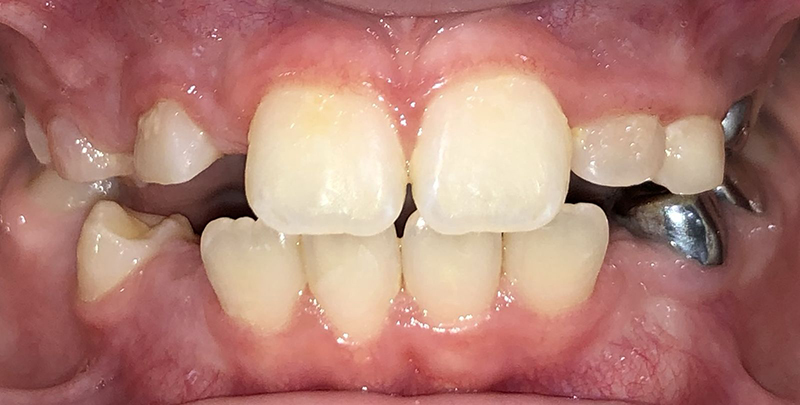

Actual Patient: Bailey

Before

Severe “Overbite”, BUCK TEETH, Narrow Jaws, Severe Deep Bite

Front View

Treatment Time: 7.5 months